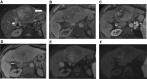

Hepatocellular carcinoma (HCC) is one of the most common tumors worldwide, usually occurring on a background of liver cirrhosis. HCC is a highly vascular tumor in which angiogenesis plays a major role in tumor growth and spread. Tumor-induced angiogenesis is usually related to a complex interplay between multiple factors and pathways, with vascular endothelial growth factor being a major player in angiogenesis. In the past decade, understanding of tumor-induced angiogenesis has led to the emergence of novel anti-angiogenic therapies, which act by reducing neo-angiogenesis, and improving patient survival. Currently, Sorafenib and Lenvatinib are being used as the first-line treatment for advanced unresectable HCC. However, a disadvantage of these agents is the presence of numerous side effects. A major challenge in the management of HCC patients being treated with anti-angiogenic therapy is effective monitoring of treatment response, which decides whether to continue treatment or to seek second-line treatment. Several criteria can be used to assess response to treatment, such as quantitative perfusion on cross-sectional imaging and novel/emerging MRI techniques, including a host of known and emerging biomarkers and radiogenomics. This review addresses the pathophysiology of angiogenesis in HCC, accurate imaging assessment of angiogenesis, monitoring effects of anti-angiogenic therapy to guide future treatment and assessing prognosis.